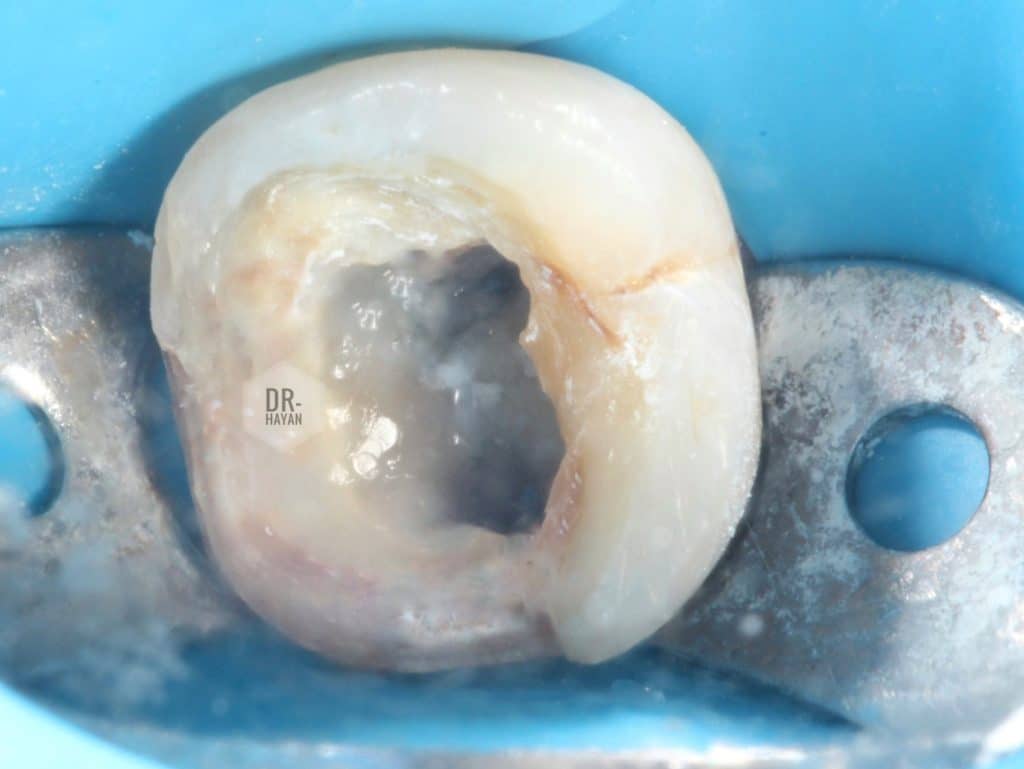

After isolation :

Under magnification I can see different colors of white dentin over the entry of canal

Here , you need

- Sharp explorer probe

- Ulra sonic endo tip ( diamond coated)

- good illumination

After some minutes, I found it

Deep split mb & ml canal